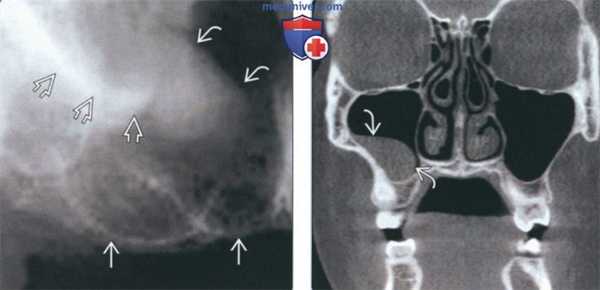

Рис. 2. МСКТ. Коронарная (а) и сагиттальная (б) реконструкции правого верхнечелюстного синуса пациента К., 29 лет. Диагноз: правосторонний одонтогенный хронический верхнечелюстной синусит. Корни зубов 1.6, 1.7 и 1.8 погружены в полость верхнечелюстного синуса. Состояние после эндодонтического лечения зубов 1.6 и 1.7, с выведением пломбировочного материала за верхушку небного корня 1.7. В области корней зубов 1.6 и 1.7 отмечается разрежение костной ткани с нечеткими неровными контурами (рентгенологические признаки гранулирующего периодонтита). В нижнем отделе синуса определяется пристеночное мягкотканное образование с полицикличным контуром, костные стенки синуса в данной области не прослеживаются.

Рис. 3. КЛКТ. Сагиттальная реконструкция, правый верхнечелюстной синус. Пациент У., 48 лет. Диагноз: правосторонний одонтогенный хронический верхнечелюстной синусит. Зубы 1.6 и 1.7 после эндодонтического лечения, отмечается выведение пломбировочного материала за верхушки корней зуба 1.6 (материал располагается в костной ткани альвеолярного отростка и в подслизистом слое синуса). Определяется разрежение костной ткани в области корней 1.6 и 1.7, костная стенка синуса в данной области не прослеживается (стрелка). В нижнем отделе синуса определяется утолщение слизистой оболочки до 10 мм, в верхнемедиальном отделе синуса визуализируется инородное тело неправильной формы металлической плотности (соответствует фрагментам пломбировочного материала).